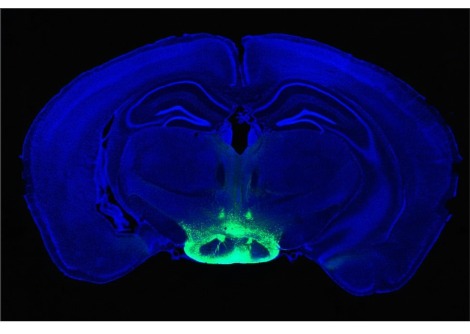

إنّ إهتزاز الجسم بالكامل ينقل الطاقة للجسم عن طريق انقباض وارتخاء العضلات عدّة مرّات في الثانية، تساعد هذه العمليّة كما يقول العلماء على تحفيز الهرمونات والقلب والأوعيّة الدمويّة بالإضافة إلى النّظام العصبي. ولأنّ الدراسات السابقة كانت قد أظهرت تأثيرات إيجابية على الأيض، فقد عكف العلماء على دراسة ما إذا كانت هذه العمليّة بنجاعة التمارين الريّاضيّة في معالجة حالات البدانة والسكّري.